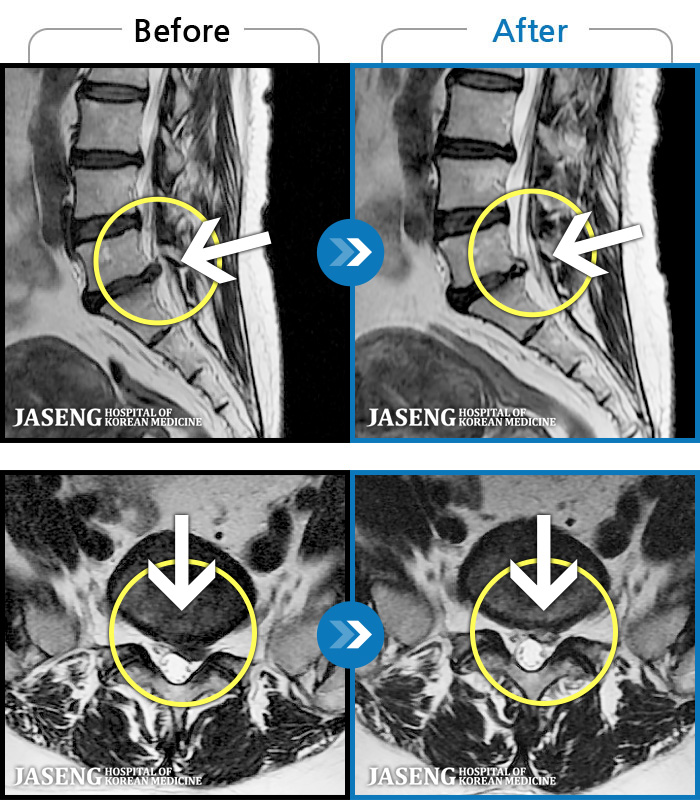

- MRI ġ

MRI ġ

1,237 MRI ũ ʸ Ȯϼ.

㸮 ϻ .